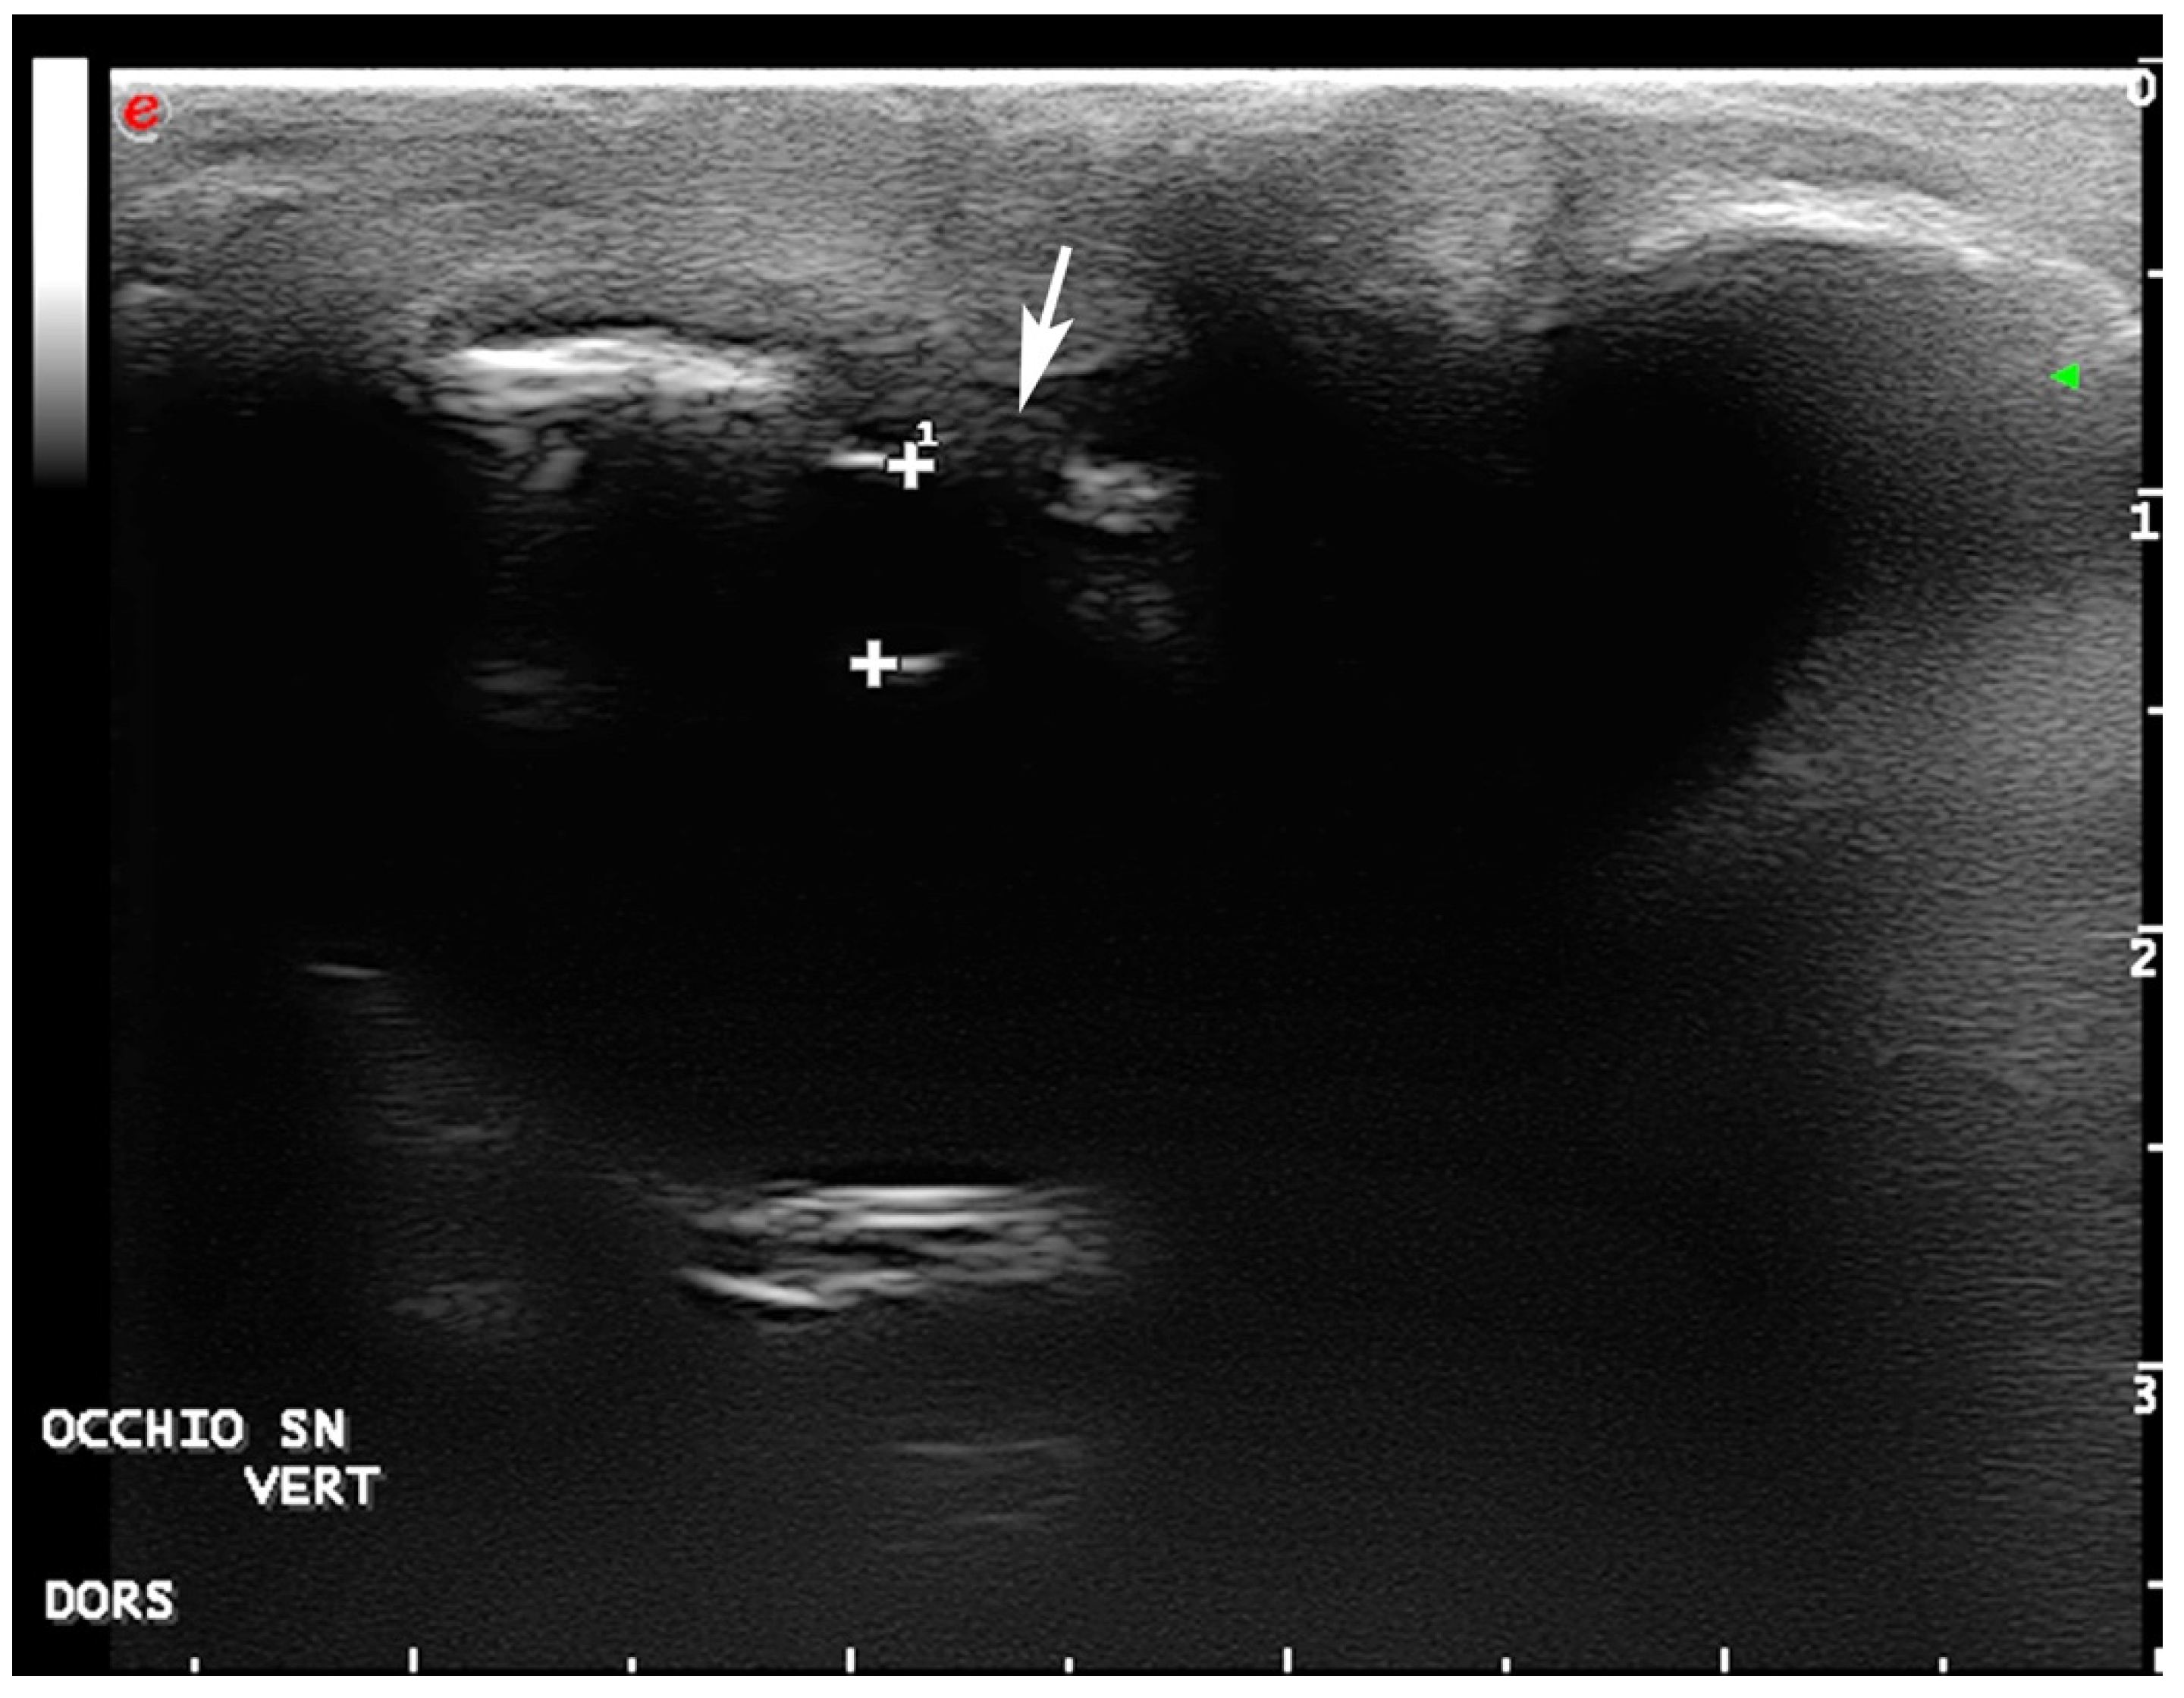

2.5. Diagnostic Imaging

- Mennonna, G.; Lamagna, B.; Affuso, A.; Greco, A.; Micieli, F.; Costanza, D.; Hochscheid, S.; Meomartino, L. Normal ultrasonographic features of loggerhead (Caretta caretta) eyes. Nat. Croat. 2020, 29 (Suppl. S1), 3–10. [Google Scholar]